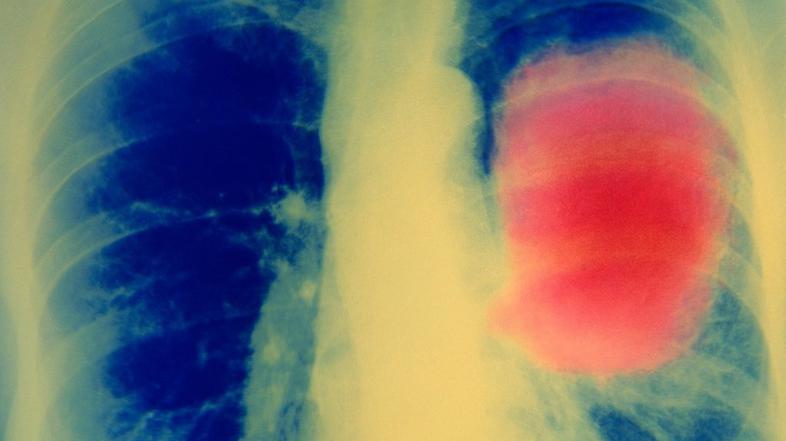

Rak na pljučih Profimedias